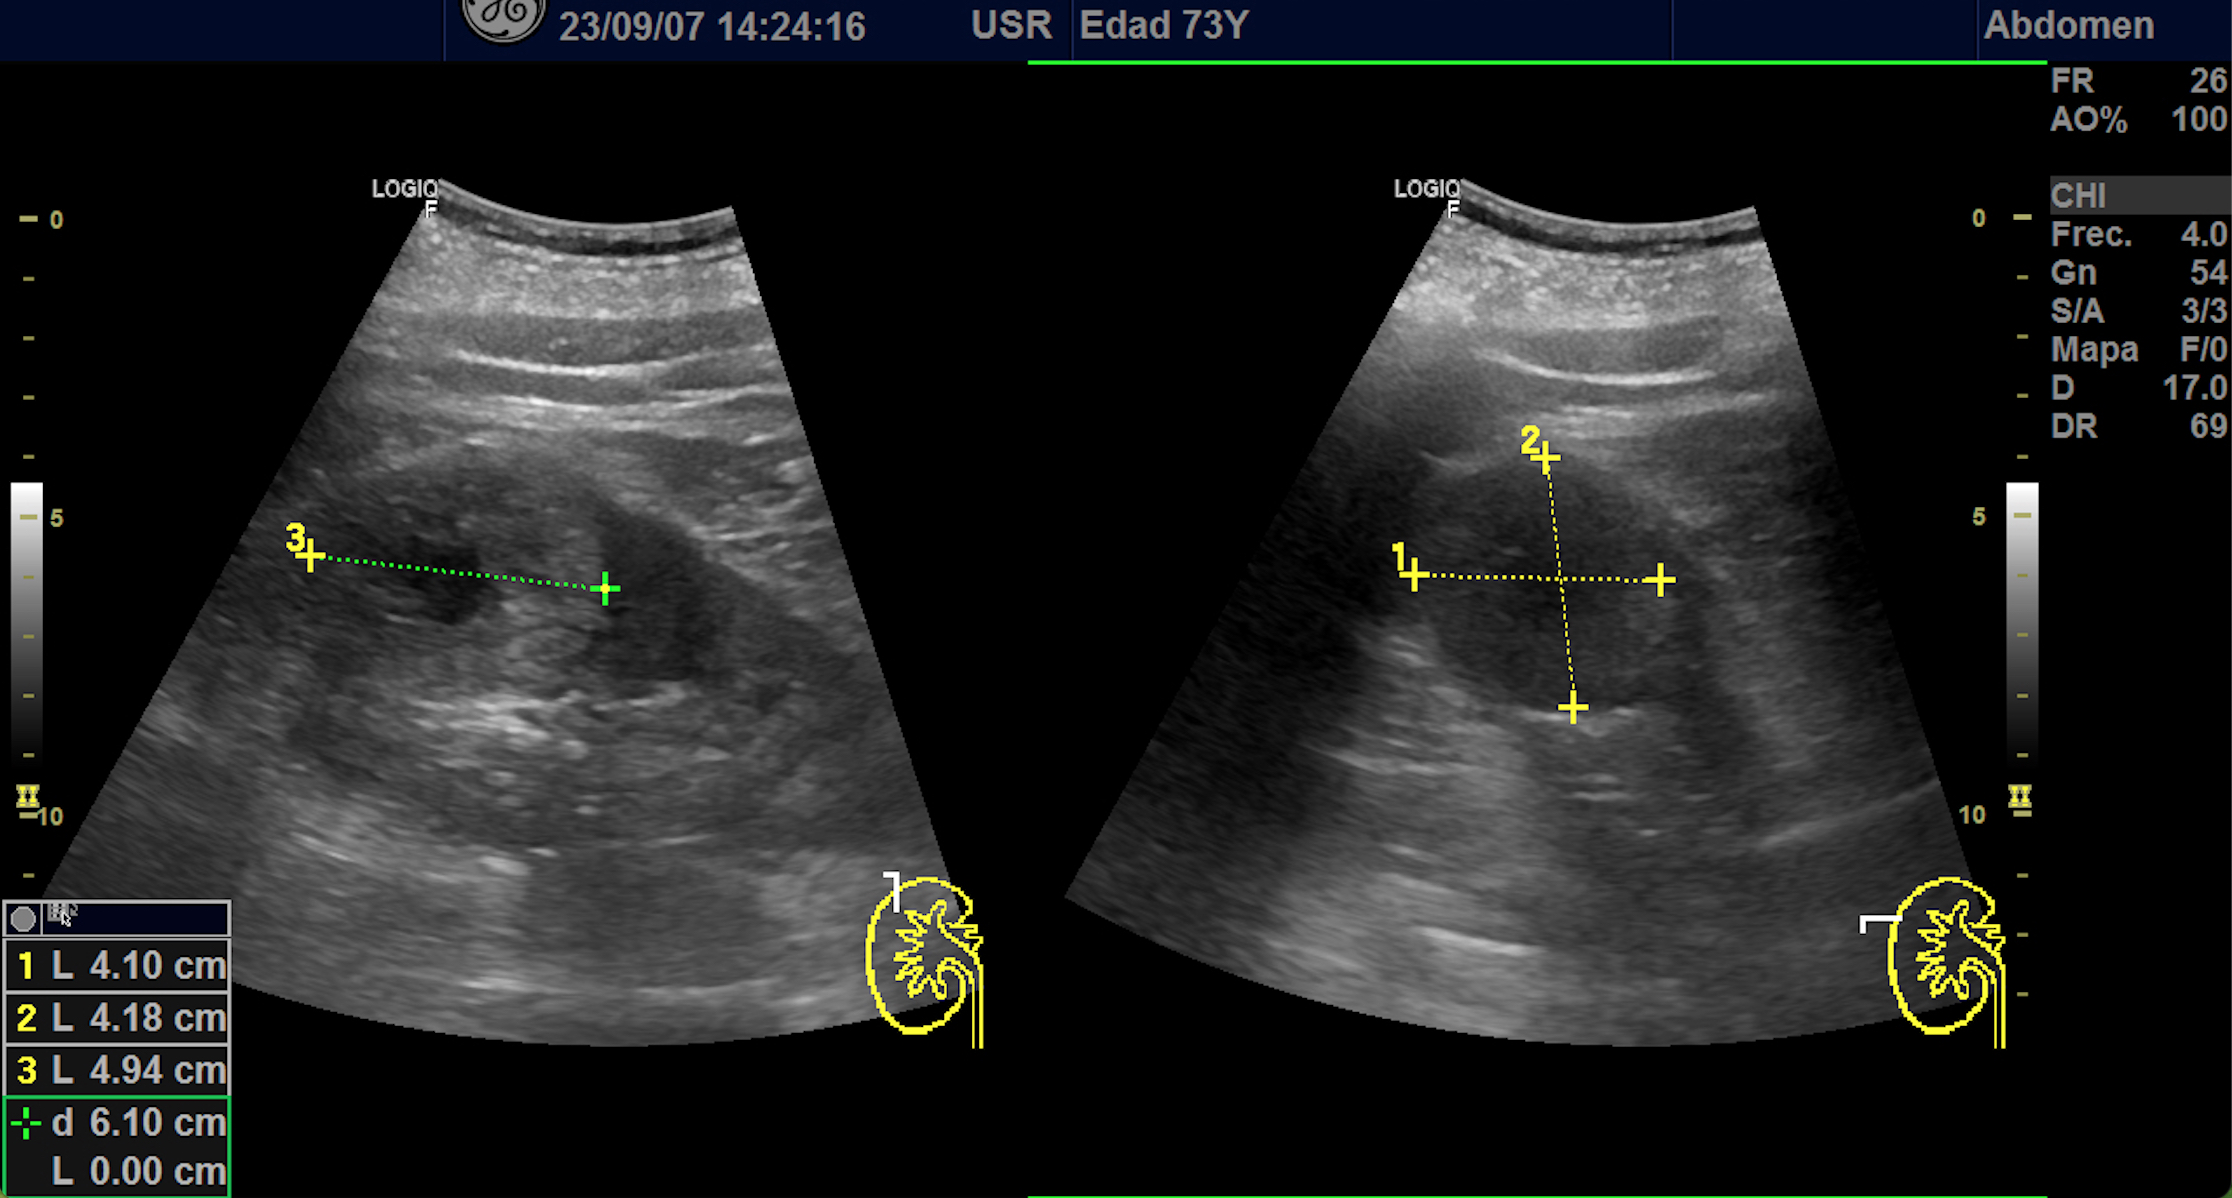

Hallazgos ecográficos

En polo superior de riñón derecho se observa una imagen redondeada, bien delimitada, isoecoica con un área central hipoecoica con vascularización periférica y central de 4,1 x 4,18 x 4,94 cm.

Riñon izquierdo sin hallazgos.